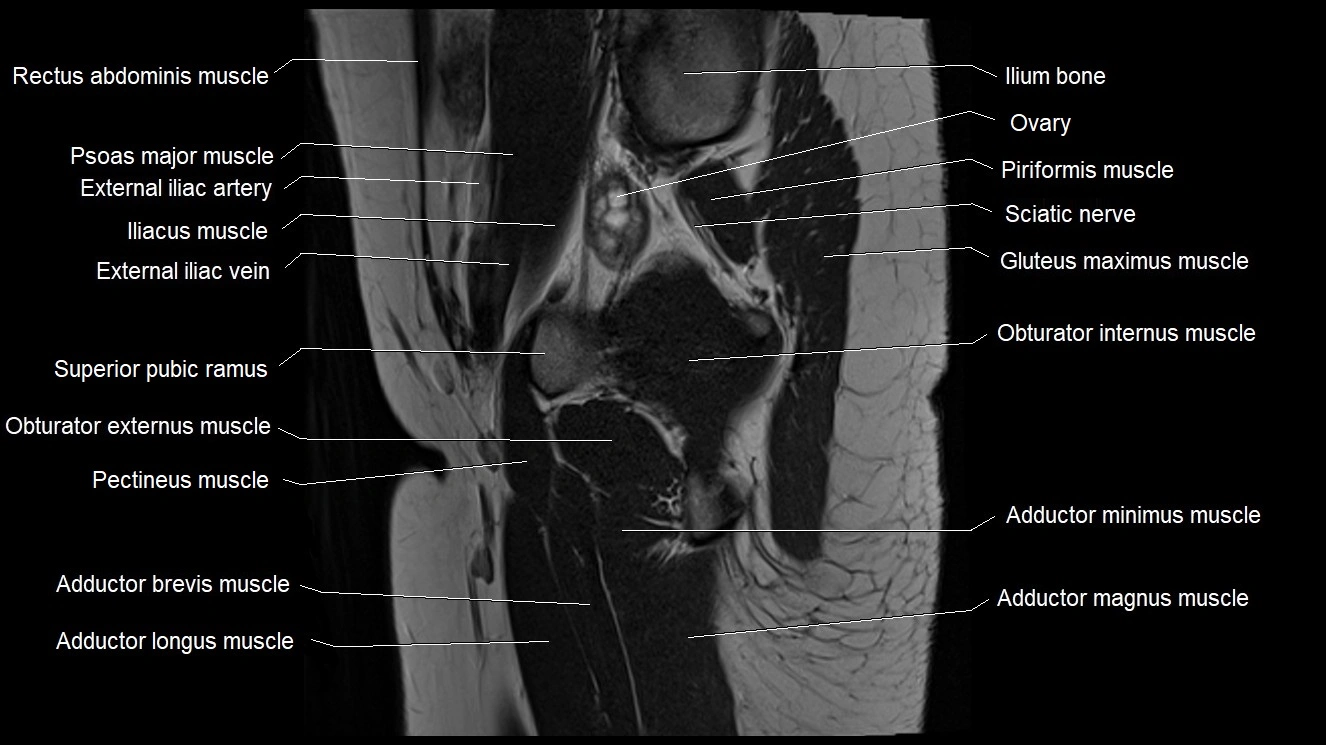

- Adductor brevis muscle

- Adductor longus muscle

- Adductor magnus muscle

- Adductor minimus muscle

- Obturator externus muscle

- Obturator internus muscle

- Pectineus muscle

- Psoas major muscle

- Superior pubic ramus